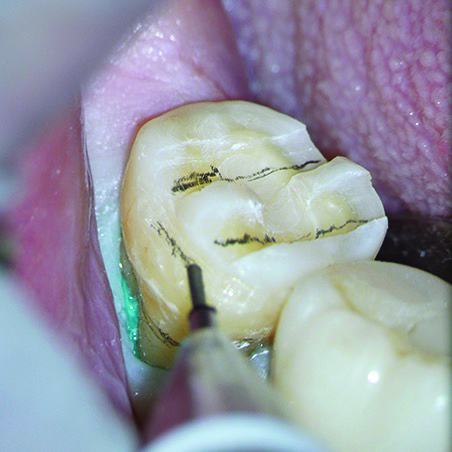

Once the cord was packed circumferentially, an additional line was marked along the previously identified finish line to provide an accurate visual reference for the tooth preparation (Figure 2). Four-handed dentistry was utilized during preparation, with the dental assistant passing hand instruments to and minimizing hand strain on the clinician. This helps enable smooth preparation from various angles while facilitating maximum control over the magnified operating field.

Fig 2. After retraction cord was packed all around the tooth under the microscope, the previous margin marks were refreshed for accurate orientation of the preparation.

Figure 2